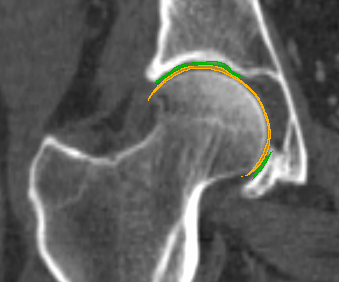

We have qualitatively verified that the articulating surfaces in all the ten HJs are detected correctly regardless of their anatomical variance using visual inspection of overlays as shown in Fig. 4. As desired, we observe a high degree of congruence between the opposing joint surfaces, meaning no gaps or overlaps in the cartilage-cartilage interface. Moreover, we observe a smooth transition towards the bone geometries as expected from the correct anatomy. The parameter values used to generate the cartilage from Fig. 5(a). The free parameters are the neighbourhood-size used to estimate the curvature of the bone (𝒩𝒩\mathcal{N}); the minimum and maximum curvature in the cartilage region (κmin,κmaxsubscript𝜅subscript𝜅\kappa_{\min},\kappa_{\max}; Eq. (2)); the distance parameter in mm𝑚𝑚mm (δ𝛿\delta; Eq. 1); and the number of times the outer boundary should be trimmed (Ntrimsubscript𝑁𝑡𝑟𝑖𝑚N_{trim}). Here, the curvature based parameters (𝒩,κmin,κmax)\mathcal{N},\kappa_{\min},\kappa_{\max}) are only used for the femur. See supplementary material for more visual comparisons.

Fig. 4 visualizes the von Mises stress pattern on the pelvic cartilage for one HJ. More are shown in the supplementary material. We have verified that no spurious stress peaks appear and that stress values change gradually and smoothly across the cartilage. Further, the high-stress areas are located in the up-direction, as we expect from the applied displacements. The stress values and patterns are not to be confused with those from a real stance. They only serve as a verification test of simulation properties. For such a simulation, we require ligaments and muscles to stabilize the girdle and a correction from sublime pose bias.

Refer to caption

(a) Von Mises stress.

(b) CT scan overlay.

Figure 4: The von Mises stress patterns ((a)) and the generated cartilage imposed on the CT scan from which the bone was extracted ((b)). Notice the high level of congruence in the cartilage-bone interfaces and cartilage-cartilage interface.